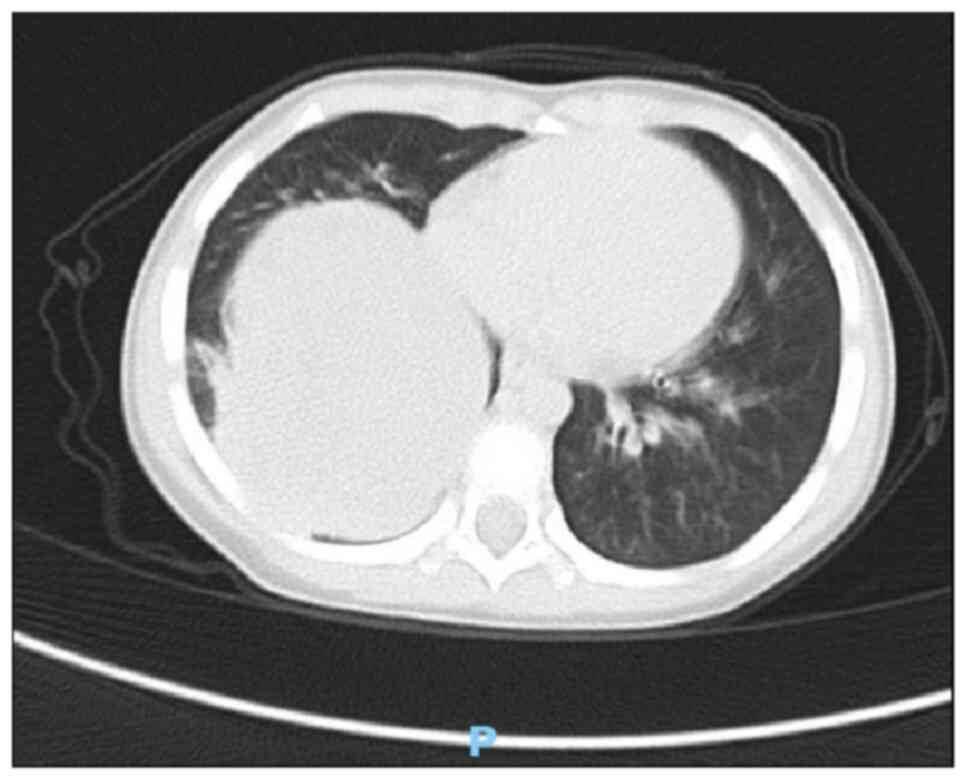

A 3-year-old female patient was admitted to the Affiliated Hospital of Zunyi Medical University (Zunyi, China) in May 2023 for further evaluation after presenting with a 2-month history of cough without obvious inducement and without symptoms including sputum, fever, chills, shortness of breath, dyspnea, abdominal pain, abdominal distension, nausea, vomiting, urinary frequency, and urgency. The symptoms had not markedly improved after oral anti-inflammatory treatment. A chest X-ray revealed bronchitis and a mass in the right thoracic cavity (data not shown), prompting a recommendation for a contrast-enhanced chest computed tomography (CT) scan. Physical examination showed a good mental state, no evident three concave signs, a stable and regular breathing rhythm, symmetrical thorax bilaterally, no pleural friction rub and no subcutaneous crepitus. The right lung exhibited hyperresonance with distinct fine moist rales. A chest CT plain scan and enhanced scan revealed a mass measuring ~85×74×68 mm in the right lower thoracic cavity with uneven density, clear boundaries, and significant heterogeneous enhancement on the contrast-enhanced scan (Figs. 1 and 2). Multiple tortuous vascular shadows were noted within the mass. The right lower lobe was compressed, and flaky increased density shadows were observed in the right middle and lower lobes. The mediastinum remained centered, with no enlarged lymph nodes in the mediastinum or bilateral pulmonary hila. The size and morphology of the heart appeared normal. These findings indicated a space-occupying lesion in the right thoracic cavity, which was considered a neoplastic lesion likely representing PPB.

Figure 1.

Chest CT plain scan shows a mass of ~85×74×68 mm in size in the lower right chest with uneven density and clear boundaries.

Imaging examinations, particularly chest CT scans, are valuable in differentiating the characteristics of lung lesions. These scans can not only identify the heterogeneity of PPB but also provide diagnostic insights into the presence of pleural effusion and chest wall invasion. For larger masses, a biopsy can be performed under CT guidance to confirm the diagnosis (15). In the present case, CT revealed a right lung mass identified as a neoplastic lesion, possibly indicative of PPB. Differentiation between neurogenic tumors and germ cell-derived tumors is necessary and should be corroborated with clinical and pathological findings. Typically, PPB presents as a solitary, well-defined mass that can exceed 10 cm (13). Based on histological variations, CT scans display different imaging characteristics. Type I PPB lesions often appear as single or multiple subpleural or intrapulmonary cystic masses, requiring differential diagnosis from other cystic lesions such as bronchogenic cysts, pulmonary cysts, pulmonary bullae and interstitial emphysema. Type II PPB frequently presents as intrapulmonary cystic and solid masses, whilst type III PPB predominantly manifests as solid lesions with uniform density and clear boundaries. The differential diagnosis of type II and III PPB, especially when locally invasive, often necessitates differentiation from other malignant tumors, such as neuroblastoma, Ewing's sarcoma and rhabdomyosarcoma. Although CT provides valuable reference data for clinicians and pathologists in diagnosing PPB, it is not definitive, and the final diagnosis relies on pathological examination (3,4).